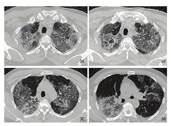

患者既往有前列腺增生病史,否认高血压、糖尿病、冠心病、慢性支气管炎等病史,否认输血史。未婚未育,有冶游史。入院后完善相关检查,继续给予莫西沙星抗感染、丙种球蛋白加强免疫和甲强龙抗炎治疗。患者平静状态下SpO2维持在95%~98%,活动后SpO2维持在92%~93%。2月2日复查胸部CT示:两肺大片炎症,较2020年1月31日仍有进展,病毒性肺炎可能(见图3)。查阅患者既往就诊资料发现,该患者曾于2016年8月31日因右肾上腺腺瘤住院手术,血清梅毒抗体阳性,人类免疫缺陷病毒(HIV)阴性。2017年3月20日因发热咳嗽来本院门诊就诊,胸部CT示左下肺病毒性肺炎可能。鉴于患者梅毒抗体阳性,既往有病毒性肺炎可能病史,考虑存在免疫功能低下可能。遂于2月3日检测免疫指标示:梅毒抗体阳性,HIV抗体非阴性,待复查。后请上海市公共卫生中心专家会诊,考虑HIV造成的卡氏肺孢子菌重症肺炎可能,转至上海市公共卫生中心进一步诊疗。患者目前接受艾滋病治疗方案,症状明显改善。

本例为中年男性患者,未婚未育,有冶游史,HIV非阴性,持续咳嗽、咳痰,伴发热,临床表现为低氧血症和呼吸窘迫综合征,血常规示淋巴细胞计数进行性下降,胸部CT示两肺大片间质性炎症,渗出性磨玻璃样改变,伴肺实变,病灶呈进行性扩大,常规抗感染和抗病毒治疗效果欠佳,病情进行性加重,后经抗艾滋病治疗有效,症状改善。从临床表现、影像学改变及治疗效果考虑,最终诊断为艾滋病合并卡氏肺孢子菌重症肺炎。